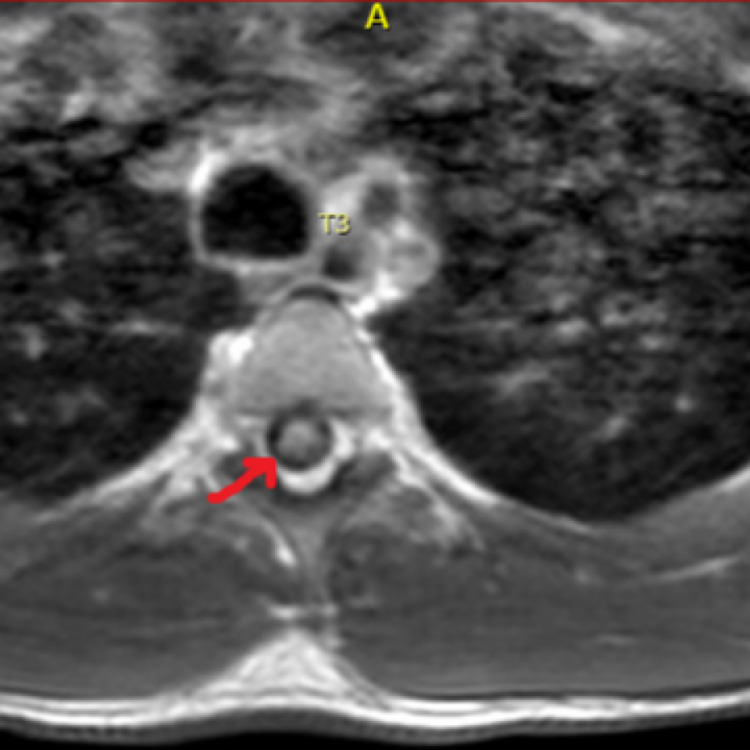

A 23-year-old male with a history of polysubstance abuse presented to the hospital with altered mental status (AMS) and hypoglycemia. He endorsed the use of alcohol, cocaine, and marijuana that day. It was confirmed with a positive toxicology screen. During this hospital admission, his physical examination was notable for paraplegia with no motor abilities from the T6 dermatome and below. Sensation was intact throughout all dermatomes but he was found to have urinary retention, which required a Foley catheter placement. Workup included an abnormal MRI showing T2 signal spanning from T2-T8, raising a high suspicion of a probable acute ischemic SCI (Figures 1, 2). MRI brain was normal, with no changes of demyelination.